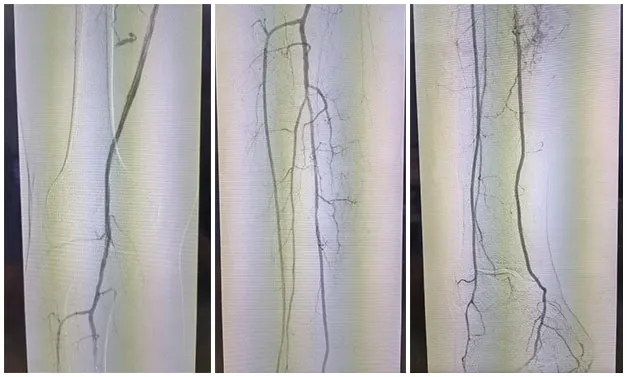

手术˜q‡ç¨‹åQ?/strong>å¯ég¸å¯¼ç®¡é…åˆå»ºç«‹é€šèµ\åŽï¼Œä½¿ç”¨2.5*150mmã€?*120mmçƒå›Šæ‰©å¼ èƒ«åŽåŠ¨è„‰ç‹­çª„ŒDµï¼Œä½¿ç”¨2*80mmã€?.5*150mmçƒå›Šæ‰©å¼ è…“动脉狭½H„段åQŒé¢„扩åŽä½¿ç”¨¾U¦æŸåž‹è¯ç‰©çƒå›?*120mmã€?*150mm分别扩张胫åŽåŠ¨è„‰ã€è…“åŠ¨è„‰ã€‚å¤æŸ¥é€ åª„½Cºå†…膜光滑,无造媄剂外渗,è†ä¸‹˜qœç«¯åŠ¨è„‰ä¸¤æ”¯æ˜‘Öª„è‰¯å¥½ã€‚æ‰‹æœ¯é¡ºåˆ©ï¼Œæœ¯åŽæ‚£è€…安˜q”ç—…æˆÑ€?/p>

手术˜q‡ç¨‹åQ?/strong>å¯ég¸å¯¼ç®¡é…åˆå»ºç«‹é€šèµ\åŽï¼Œä¿æŠ¤ä¼žä¸‹ä½¿ç”¨4*150mmçƒå›Šé¢„扩张病å˜ï¼Œåˆ†åˆ«äº¤æ¢5*200mm¾U¦æŸåž‹è¯ç‰©çƒå›Šæ‰©å¼ é—­å¡žæ®µåŠè‚¡‹¹…动脉上ŒD늋­½H„处åQ?*150mm¾U¦æŸåž‹è¯ç‰©çƒå›Šæ‰©å¼ èƒ«è…“干开å£ä¸ŠŒDµï¼Œéž˜å†…造媄昄¡¤ºè‚¡æµ…å¼€å£å¤„有残余狭½H„,余闭塞段完全å¤é€šï¼Œå†…膜光整åQŒè¡€‹¹é€šç•…åQŒå¼•å…¥DES6*40m支架一枚予以股‹¹…å¼€å£å¤„释放åQŒå¤æŸ¥é€ åª„æç¤ºç‹­çª„解除åQŒæœªè§é€ åª„剂外渗,è†ä¸‹˜qœç«¯åŠ¨è„‰å„分支显å½Þp‰¯å¥½ï¼Œæœªè§æ˜Žæ˜¾æ “å¡žã€‚æ‰‹æœ¯é¡ºåˆ©ï¼Œæœ¯åŽæ‚£è€…安˜q”ç—…æˆÑ€?/p>

以上病例åQŒæœ¯ä¸­å›¢é˜Ÿå‡é€šè¿‡¾U¦æŸåž‹è¯çƒæˆåŠŸå¼€é€šç—…å˜è¡€½Ž¡ï¼Œæœ¯åŽè¡€‹¹æ¢å¤è‰¯å¥½ï¼Œæ›²ä¹ä¸°æ•™æŽˆè¡¨½C?”¾U¦æŸåž‹è¯çƒé€šè¿‡â€˜ä»‹å…¥æ— æ¤å…¥â€™ç†å¿µï¼Œå®žçŽ°äº†â€˜ç²¾å‡†ç»™è¯â€™ä¸Žâ€˜ç‰©ç†æˆå½¢â€™çš„ååŒæ•ˆæžœåQŒå°¤å…‰™€‚åˆòq´è½»æ‚£è€…或支架¼›å¿Œç—‡äh¾Ÿ¤ï¼Œæ˜¯è¡€½Ž¡ä»‹å…¥æ²»ç–—çš„é‡è¦æŠ€æœ¯è¡¥å……ã€?#8221;